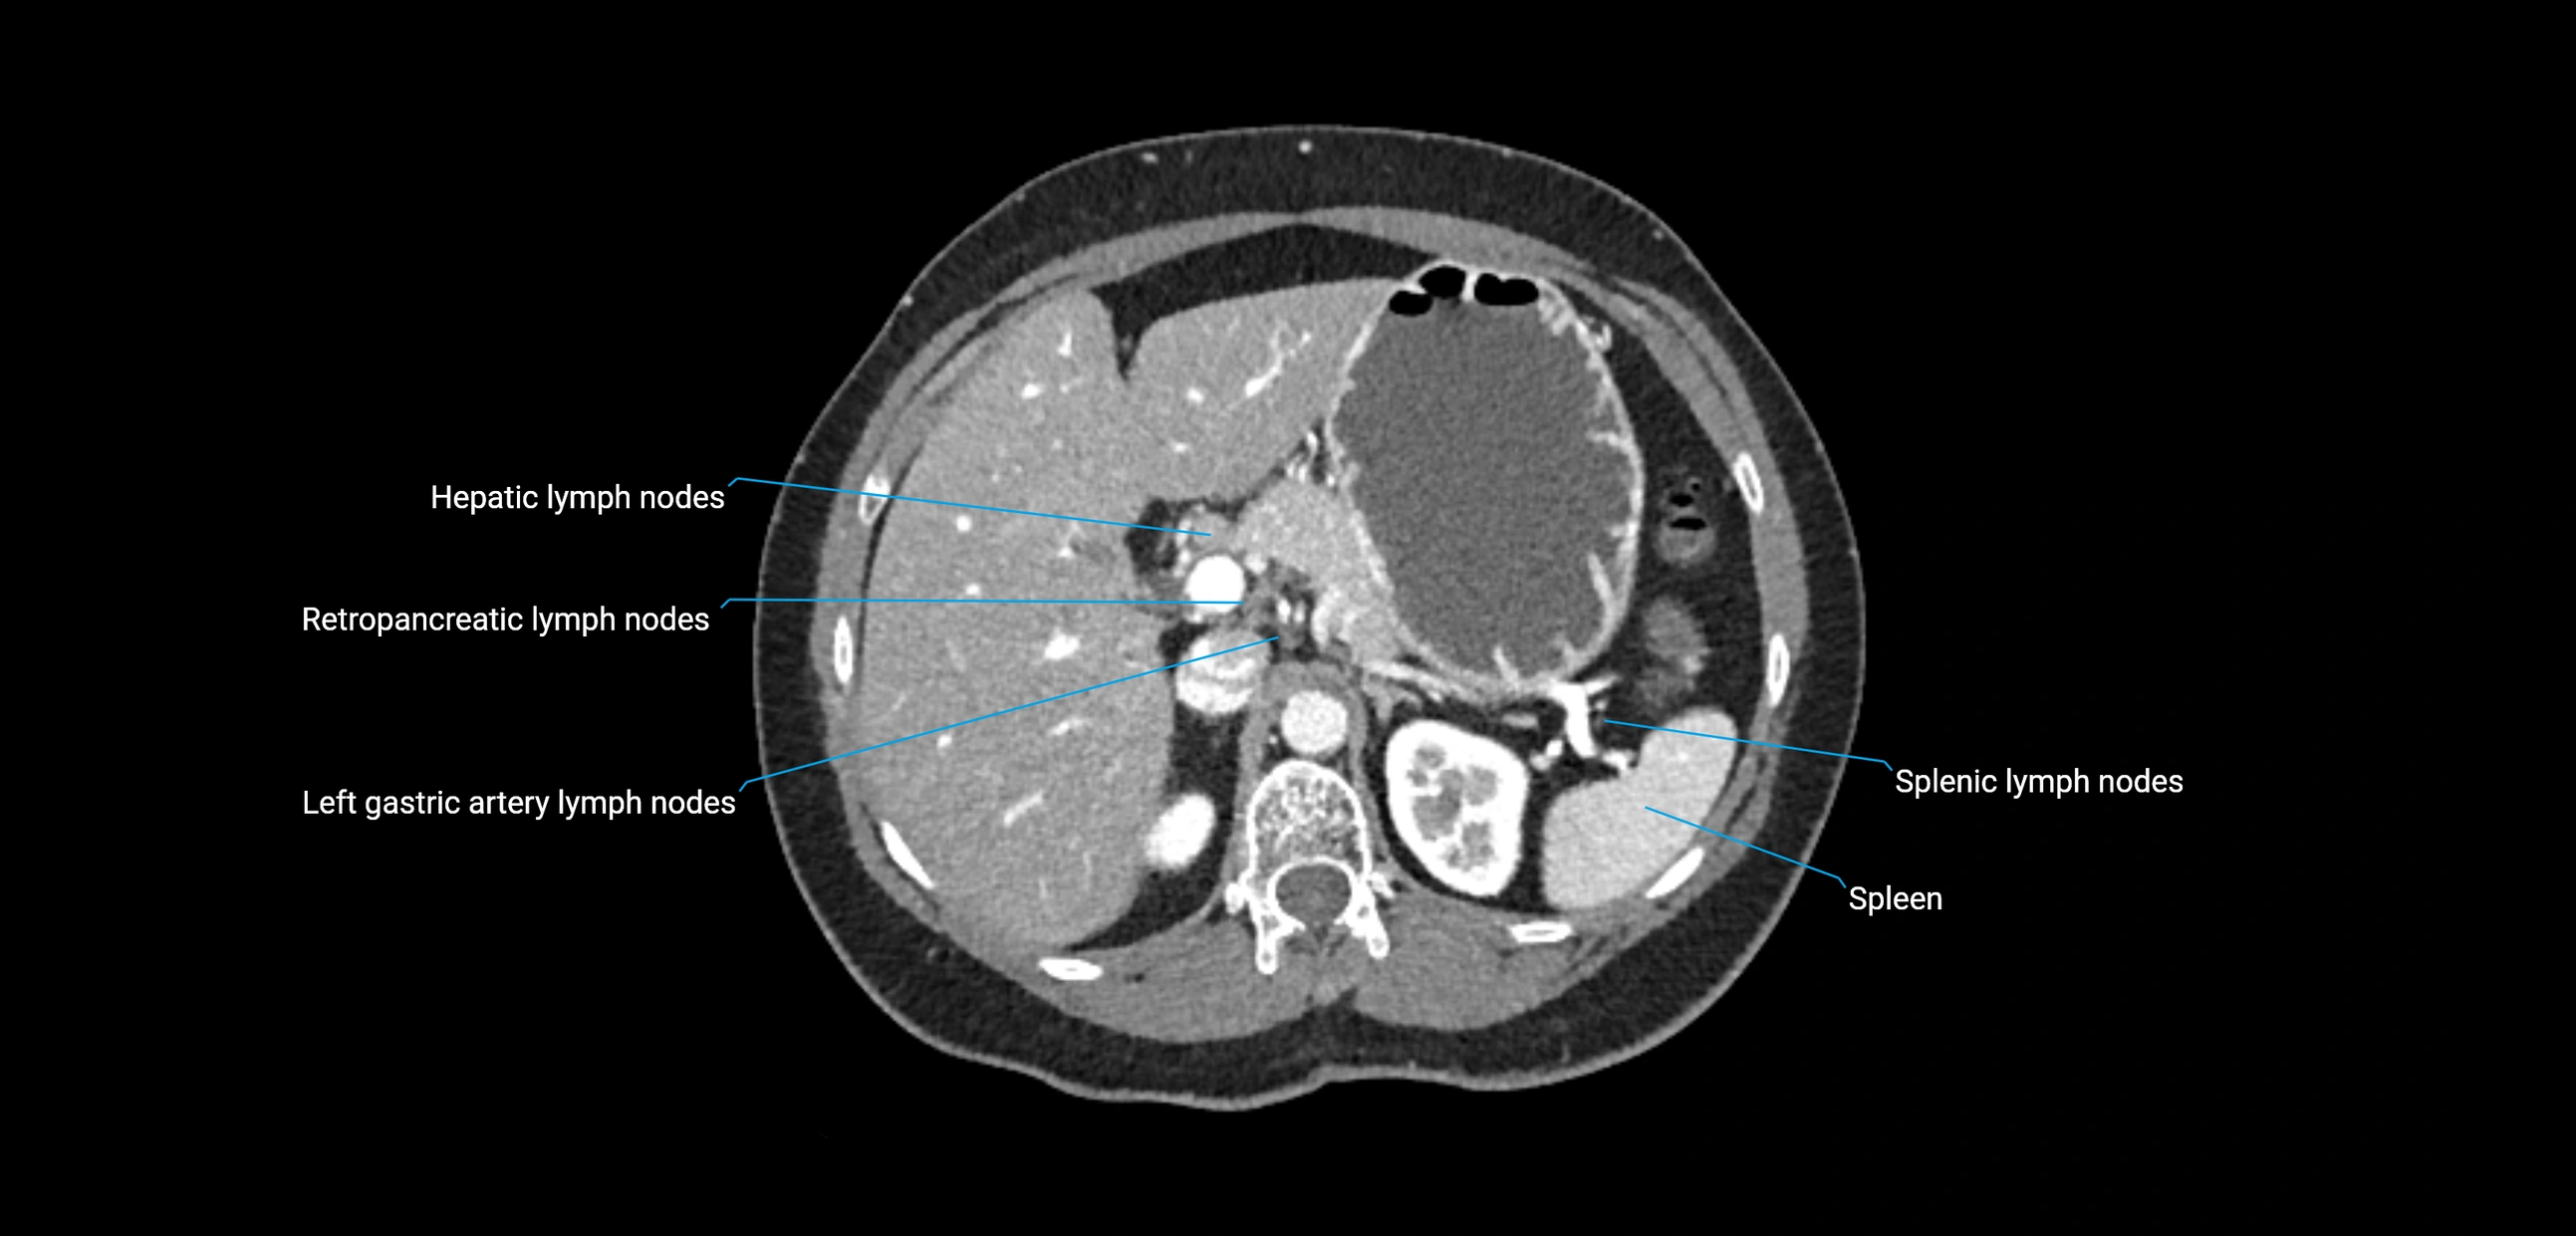

The lateral aortic lymph nodes (also called para-aortic lymph nodes) are a major group of retroperitoneal lymph nodes located along the abdominal aorta and its branches. They lie between the diaphragmatic crura superiorly and the bifurcation of the aorta at L4 inferiorly.

These nodes receive lymph from a wide range of abdominal and pelvic structures. Specifically, they drain lymph from the kidneys, suprarenal glands, gonads (testes/ovaries), uterus, uterine tubes, and pelvic organs, before converging into the lumbar lymphatic trunks, which terminate in the cisterna chyli → thoracic duct.

CT image

image